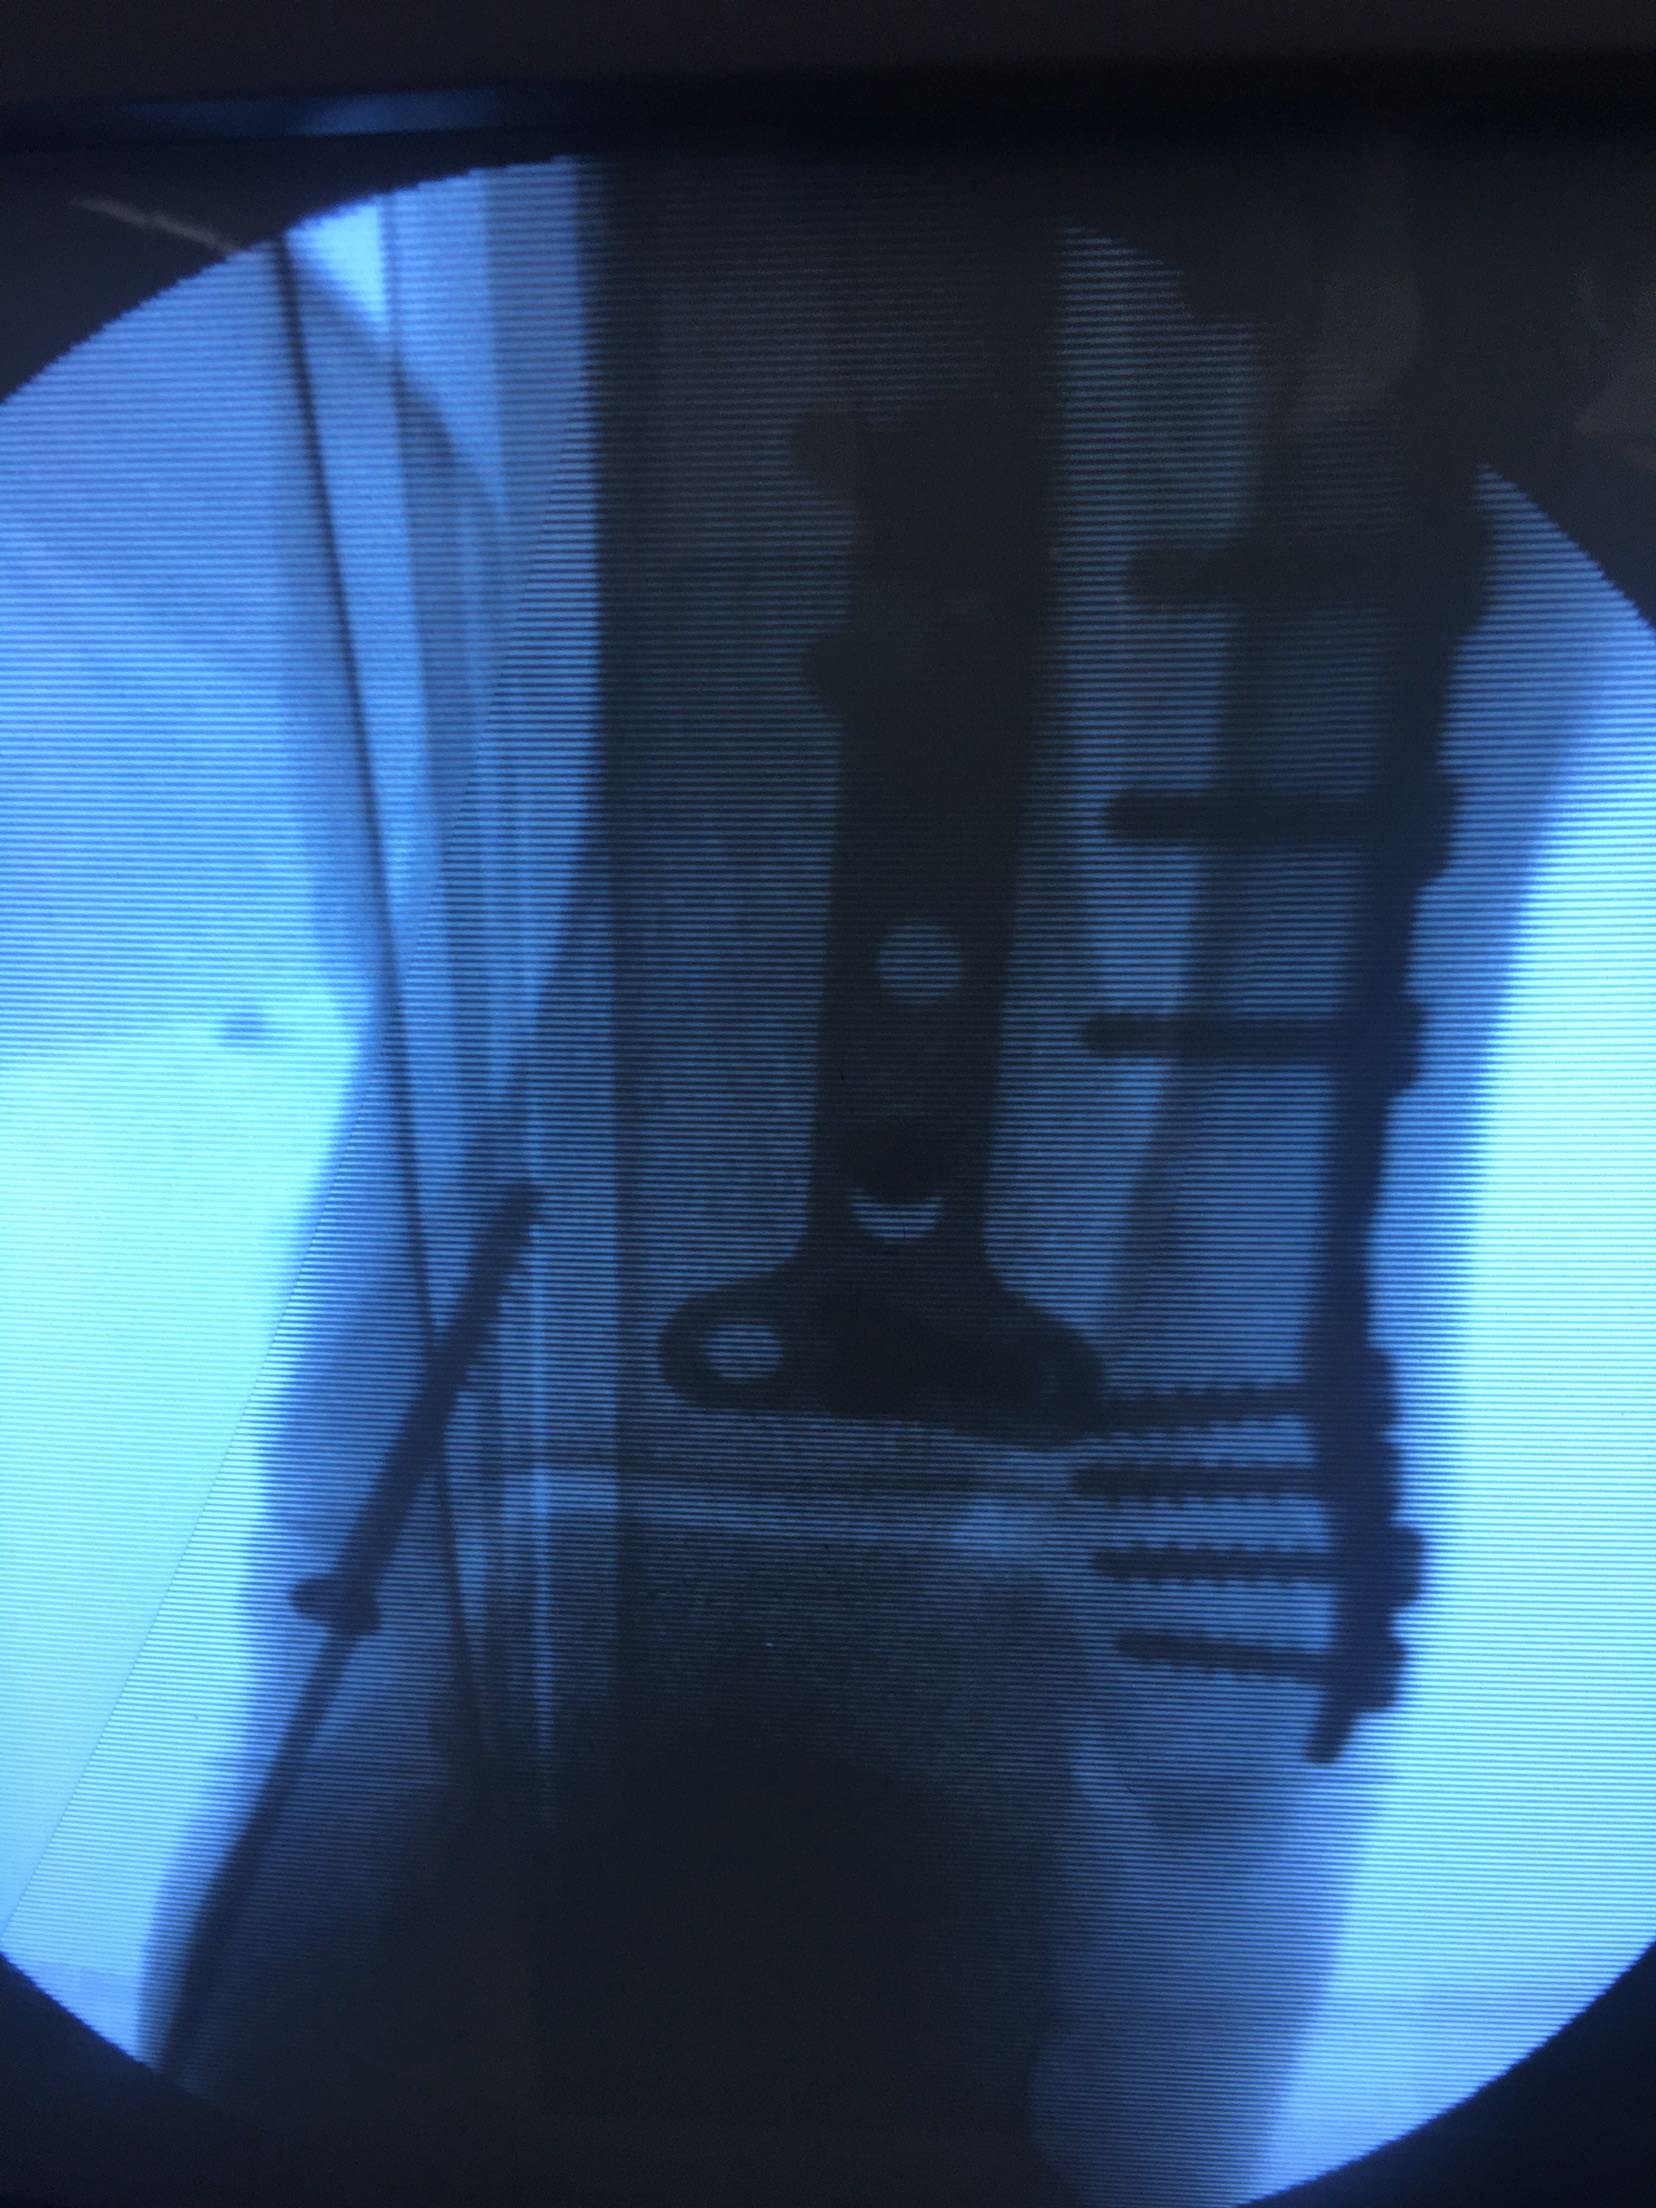

三踝粉碎性骨折(切复内固定)

患者,男,37岁,摔伤后右踝肿痛,畸形,活动受限3小时入院。既往身体健康,无特殊不良嗜好。

右踝部肿胀明显,局部皮色发红,皮温高,畸形,环形压痛,纵叩痛,末梢血运感觉正常,余未见异常。

急诊行跟骨结节牵引,术后一周肿胀消退,在腰麻下行切复内固定术,术后制动抬高,抗炎,消肿等对症处理。